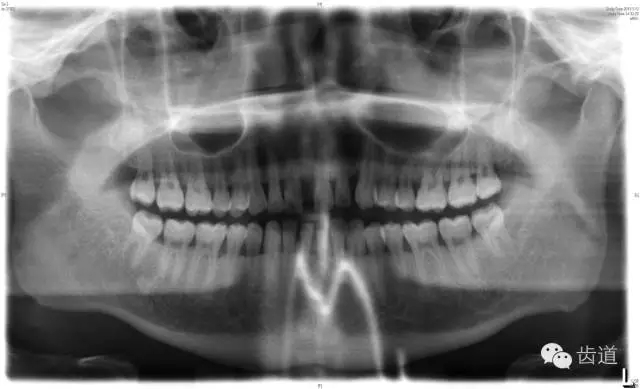

6、輔助檢查

X線:根尖片、曲面斷層片(牙槽嵴頂,水平垂直吸收,程度)

21.webp.jpg

22.webp.jpg

23.webp.jpg

大表